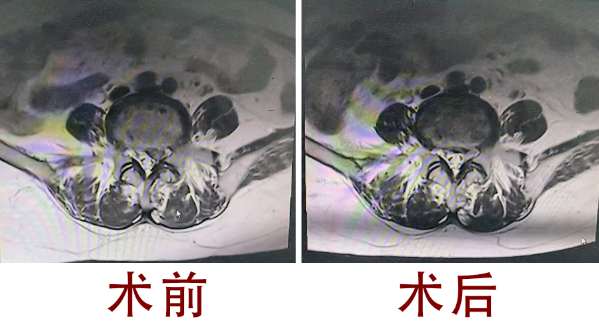

医道之光 照亮虞城丨虞城疼痛患者的福音!国家级...